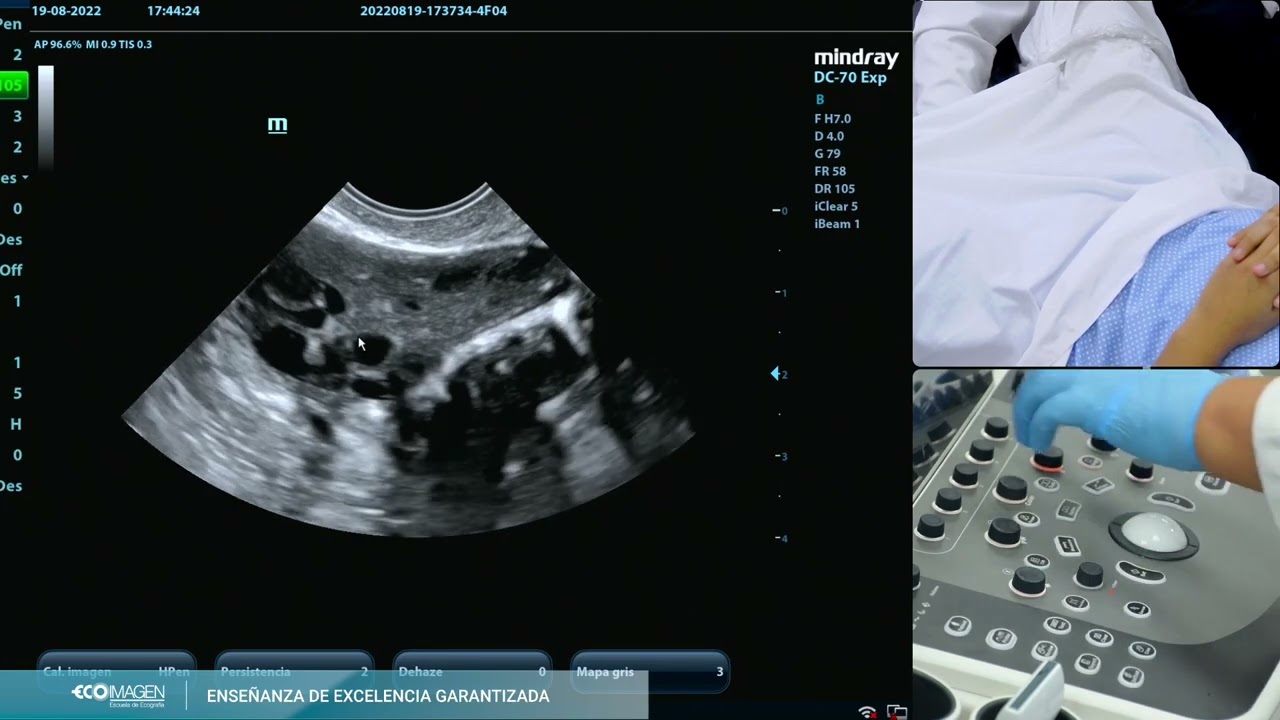

DR.TV - Ovario Poliquístico

Описание: ¿Cuánto sabe sobre los quistes en los ovarios?

¿sabe por qué se forman y qué tan peligrosos pueden llegar a ser?

La bella Dorita Orbegoso llega para aprender todo sobre un diagnóstico que ella misma recibió: Ovario Poliquístico.

SÍNDROME de OVARIO POLIQUÍSTICO: causas, síntomas y diagnóstico.   - Ginecología y Obstetricia -

DR TV PERU 21-09-2012 - 1 El Asistente del Día -- Quistes de Ovario

COMO DIAGNOSTICAR EL OVARIO POLIQUISTICO. DE UNA FORMA DIFERENTE